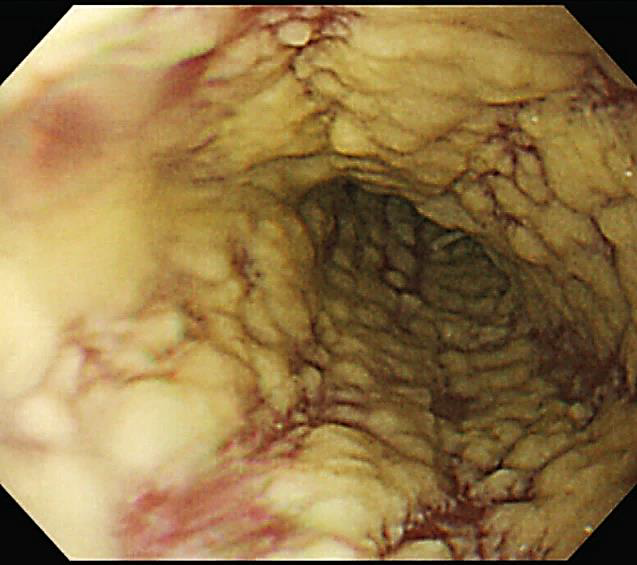

Homem, 27 anos, sem comorbidades prévias conhecidas, iniciou quadro de disfagia alta há dois meses, episódios de febre ocasional não aferida e perda de 4 Kg, a qual relacionou à dificuldade de se alimentar. Conta ainda que nos últimos cinco dias vem sentindo discreta dispneia ao caminhar e dor torácica ventilatório dependente em hemitórax direito. A febre tornou-se mais intensa e diária, atualmente aferida em 38,5 a 39°C, além de tosse produtiva com secreção amarelada e sem hemoptise. Ao exame físico, regular estado geral, presença de estertores crepitantes em base pulmonar direita. Frequência respiratória de 25 incursões por minuto, saturação de oxigênio 95%, frequência cardíaca 98 batimentos por minuto, pressão arterial 110/80 mmHg e perfusão preservada. Oroscopia, abdome, neurológico e de membros inferiores sem alterações dignas de nota. Foram solicitados os exames de investigação descritos abaixo (Figuras 6 e 7):

----------------------------------------------Figura 7. Endoscopia digestiva alta